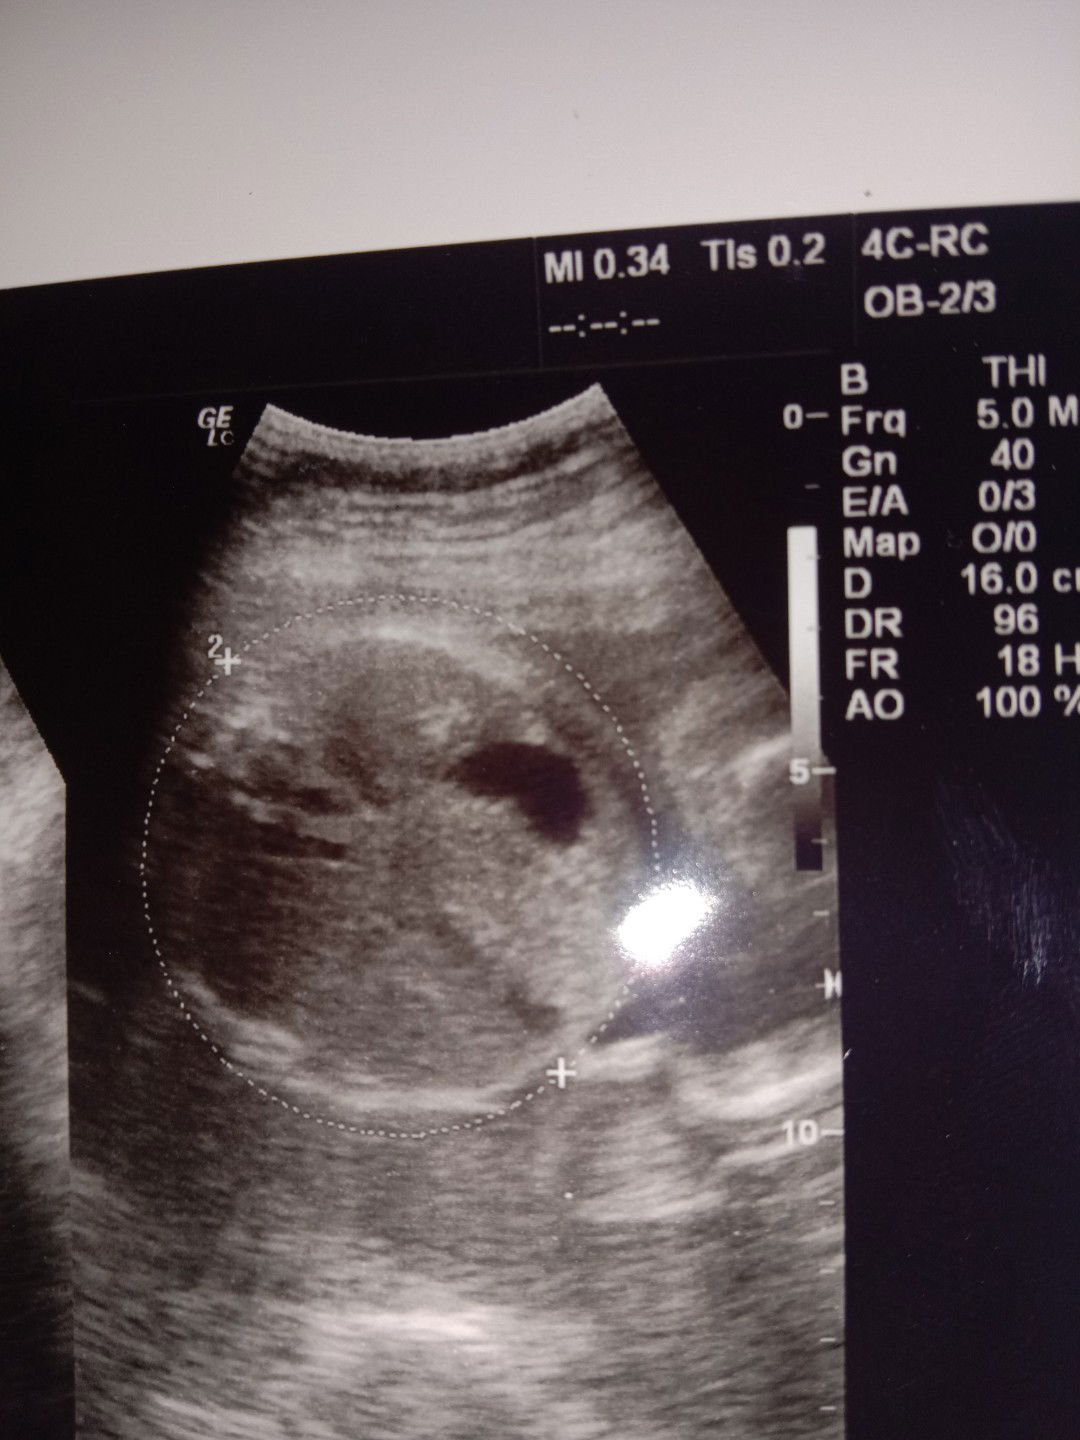

baby boy

Ini hasil usg baby boy.. Tapi sy kok ga paham itu apa ya , pas di layar keliatan monasnya pas difoto kok gitu hasilnya, ata itu telornya ya? Bunda disini ada yg bisa bantu?